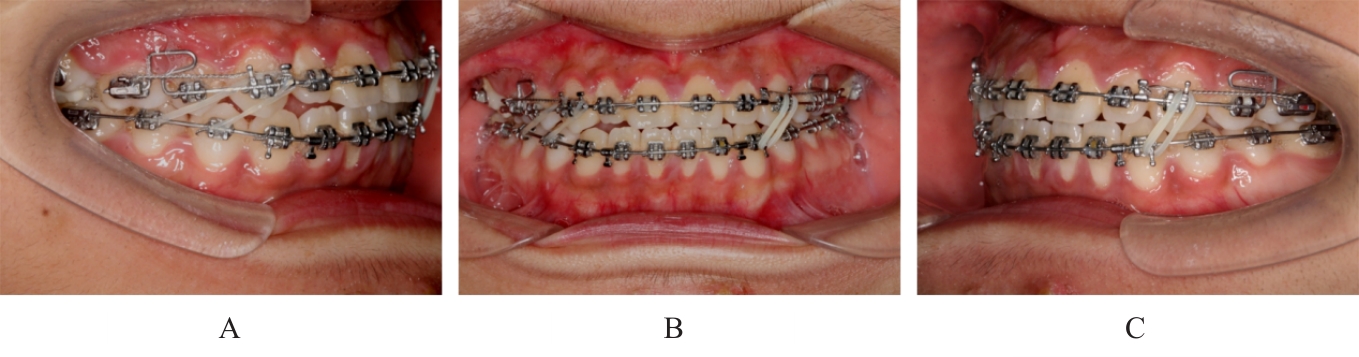

Grade Ⅲ open bite complicated with tongue hypertrophy treated by mandibular incisor extraction:A case report and literature review

Lei TIAN,Yuyan LIU,Yuqing WANG,Zhiyu ZHANG,Xiumei SUN( )

- Department of Orthodontics,Stomatology Hospital,Jilin University,Changchun 130021,China